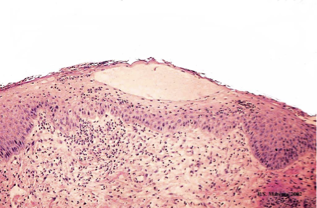

What aetiological agent causes orf (contagious pustular dermatitis)?

A poxvirus genus parapox —> orf virus

What animals does orf affect?

Young sheep and goats ; less frequently other animals (including lilehs); highly contagious but almost never lethal unless infected by scratching and leaving for agesssssssss and then having an allergic reaction to penicillin innit bruv

What is the pathogenesis of orf?

Infects keratinocytes, makes them proliferate with inflam & crust formation

How does orf present grossly?

Typical pox lesion around lips, muzzle and eye showing great degree of epidermal proliferation and crust

How does orf present histologically?

Spongiosis

Micropustules

Epidermal hyperplasia

Intra-cytoplasmic inclusion bodies